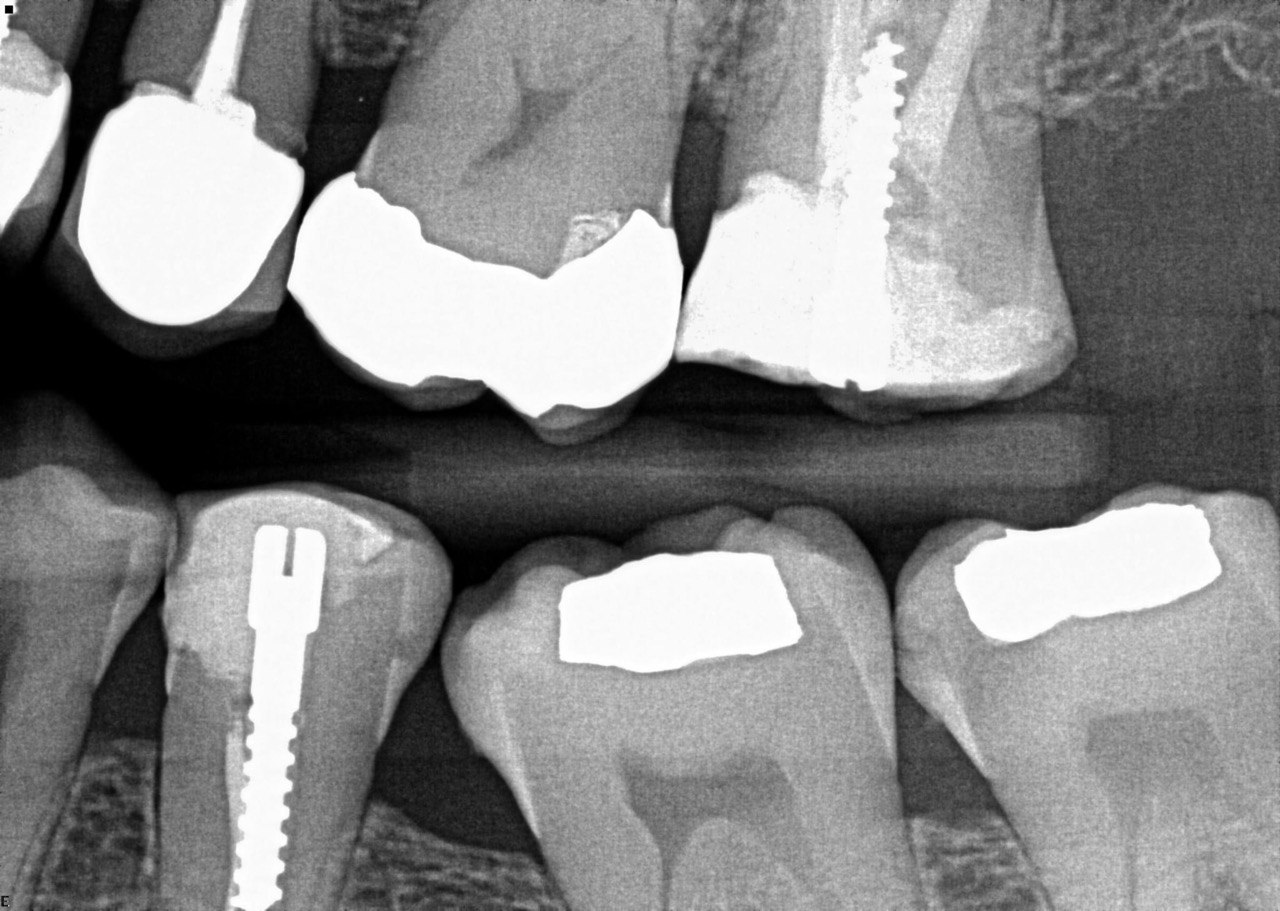

Question 4: what is the condition of the distal of the tooth # 4.1 and mesial of the tooth #3.1 respectively?

Question 5: Which surface shows recurrent caries?

Question 6: Which surface shows recurrent caries?